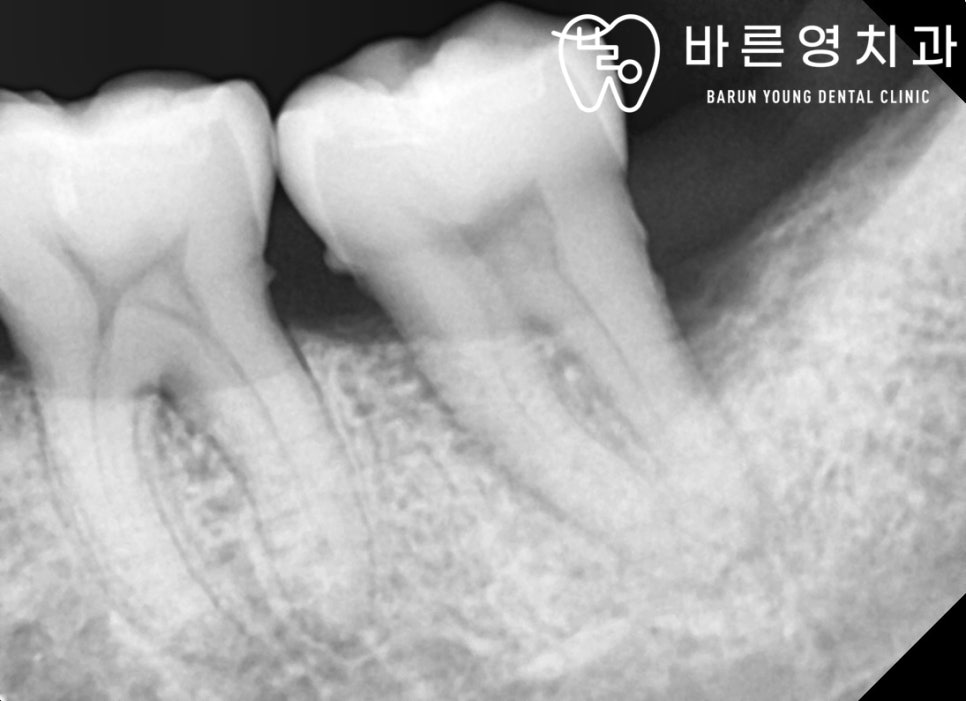

바른영치과 신경치료 사례

만약 위 단계까지 옥수역치과 충치치료를 통해 충치를 제거하지 않아 더 악화되면 충치는 상아질을 지나 치수염(치아신경)까지 퍼지게 되는데요. 이 시기는 이미 충치가 치아신경을 오염시켜 염증이 발생한 상태이기 때문에 보다 난도 높은 옥수역치과 신경치료를 진행하게 됩니다.

오염된 신경을 제거하고, 해당 빈 공간에 보충재를 채우는 신경치료 단계는 이미 자연치아가 절반 이상 손상된 상태이기 때문에 보충재만 채워서는 자연치아 저작기능을 수행하기에는 많이 약해진 상태입니다. 하여 신경치료 이후에는 남은 자연치아를 보호하고 치아기능을 제대로 수행할 수 있도록 치아모형의 보철을 씌우는 크라운 치료를 진행하게 됩니다. 이 크라운 치료가 바로 우리가 흔히 말하는 ‘금니를 씌운다’고 표현하는 치료이며, 크라운의 종류는 금니 뿐만 아니라 치아와 심미적으로 거의 흡사하고 강도가 높은 지르코니아까지 다양합니다.

즉, 충치치료 단계 중 신경치료는 자연치아를 살릴 수 있는 마지막 단계이기에 부득이한 경우가 아니라면 신경치료를 통해 남은 자연치아를 살리고 보존하는 것이 현명합니다.